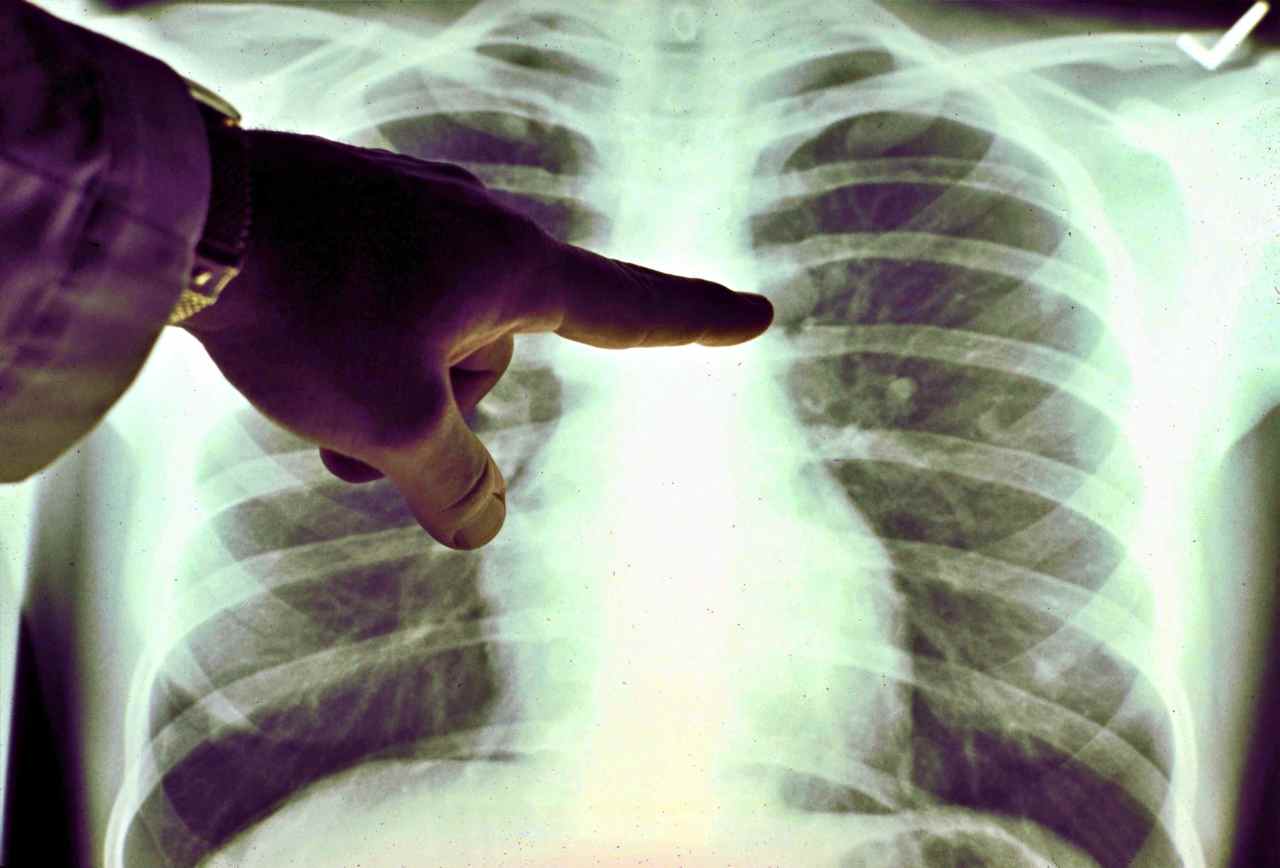

Dopo l’approvazione dell’FDA negli Stati Uniti e dell’EMA in Europa, anche l’Agenzia Italiana del Farmaco (AIFA) ha dato il via libera alla rimborsabilità di alectinib, la prima terapia a bersaglio molecolare approvata come trattamento adiuvante dopo la rimozione chirurgica in pazienti adulti con tumore del polmone non a piccole cellule (NSCLC) ALK-positivo. Si tratta di una svolta significativa per una forma rara di tumore che colpisce soprattutto pazienti più giovani e non fumatori, nei quali un riarrangiamento del gene ALK determina una proliferazione incontrollata delle cellule tumorali. Terapia mirata e nuove prospettive. 🔗 Leggi su Ilfogliettone.it